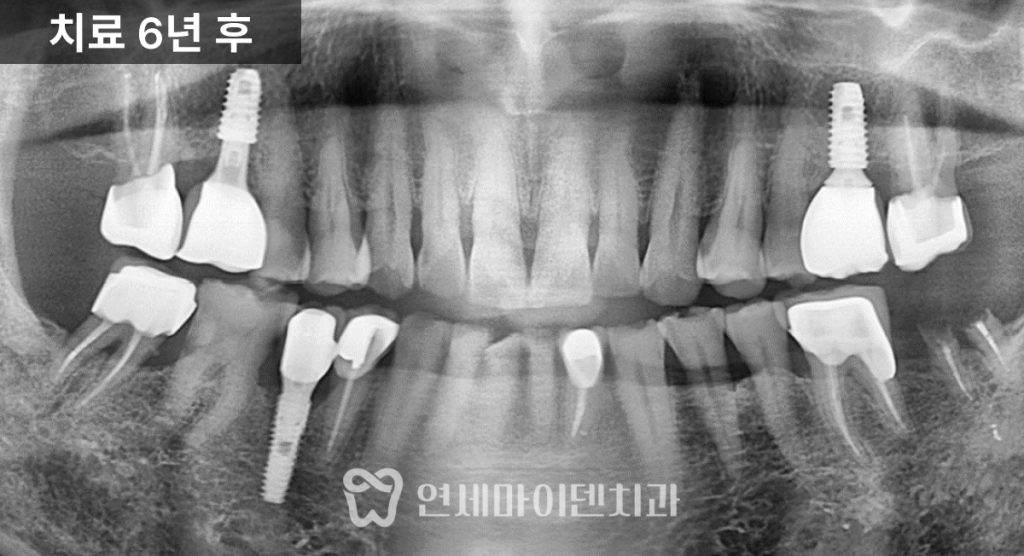

기능을 회복할 수 있었습니다.6년 경과, 보험 임플란트 장기 결과

치료가 끝난 이후에도

정기적인 검진과 관리는

매우 중요합니다.이번 케이스는

6년 이상 장기 추적 관찰을 진행했습니다.치료를 받지 않았던 일부 치아는

시간이 지나면서

추가 임플란트가 필요하게 되었지만,초기에 임플란트를 식립한 부위와

앞니 레진 수복 부위는

큰 문제 없이

안정적으로 유지되고 있었습니다.건강보험 임플란트 제도는

만 65세 이상 환자분들께

큰 도움이 되는 제도입니다.평생 두 개의 임플란트까지

보험 적용이 가능하기 때문에,

비용 부담을 줄이면서

필요한 치료를 받을 수 있습니다.중요한 점은

어디에서 치료를 받더라도

가격은 동일하다는 점입니다.

따라서 치료 결과와

장기적인 관리가 가능한

신뢰할 수 있는 의료진을

선택하는 것이 핵심입니다.또한 깨지고 닳은 앞니 수복 역시